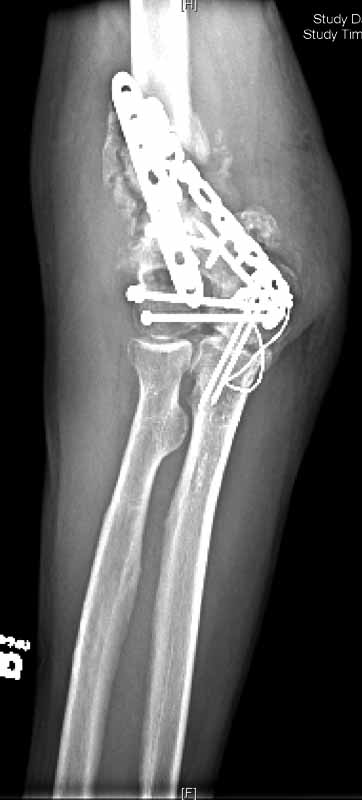

He was treated with IV antibiotics and no sign of infection was seen. After antibiotics were stopped, he still showed no sign of infection. He was offered a total elbow replacement which he refused since he has a handicapped child that he needs to care for, and he did not want to accept the lifting restrictions. He was offered an elbow fusion which he refused because he did not want the stiffness, but he did agree to fixation across the elbow without taking out the joint, even knowing that he would still have stiffness and even with later soft tissue release might not be any different than a fusion. The second revision including cross elbow fixation is in files (2nd revision).

2nd revision

This surgery was done 9/27/04. He was grafted with DBX and BMP, and debrided to bleeding bone with good contact, and compressed with a lag screw. At surgery there was no sign of infection. 3 sets of deep bone cultures came back "no growth" and a bone biopsy did not reveal any inflammatory cells. Sed rate was 21 and C-reactive protein 0.4.